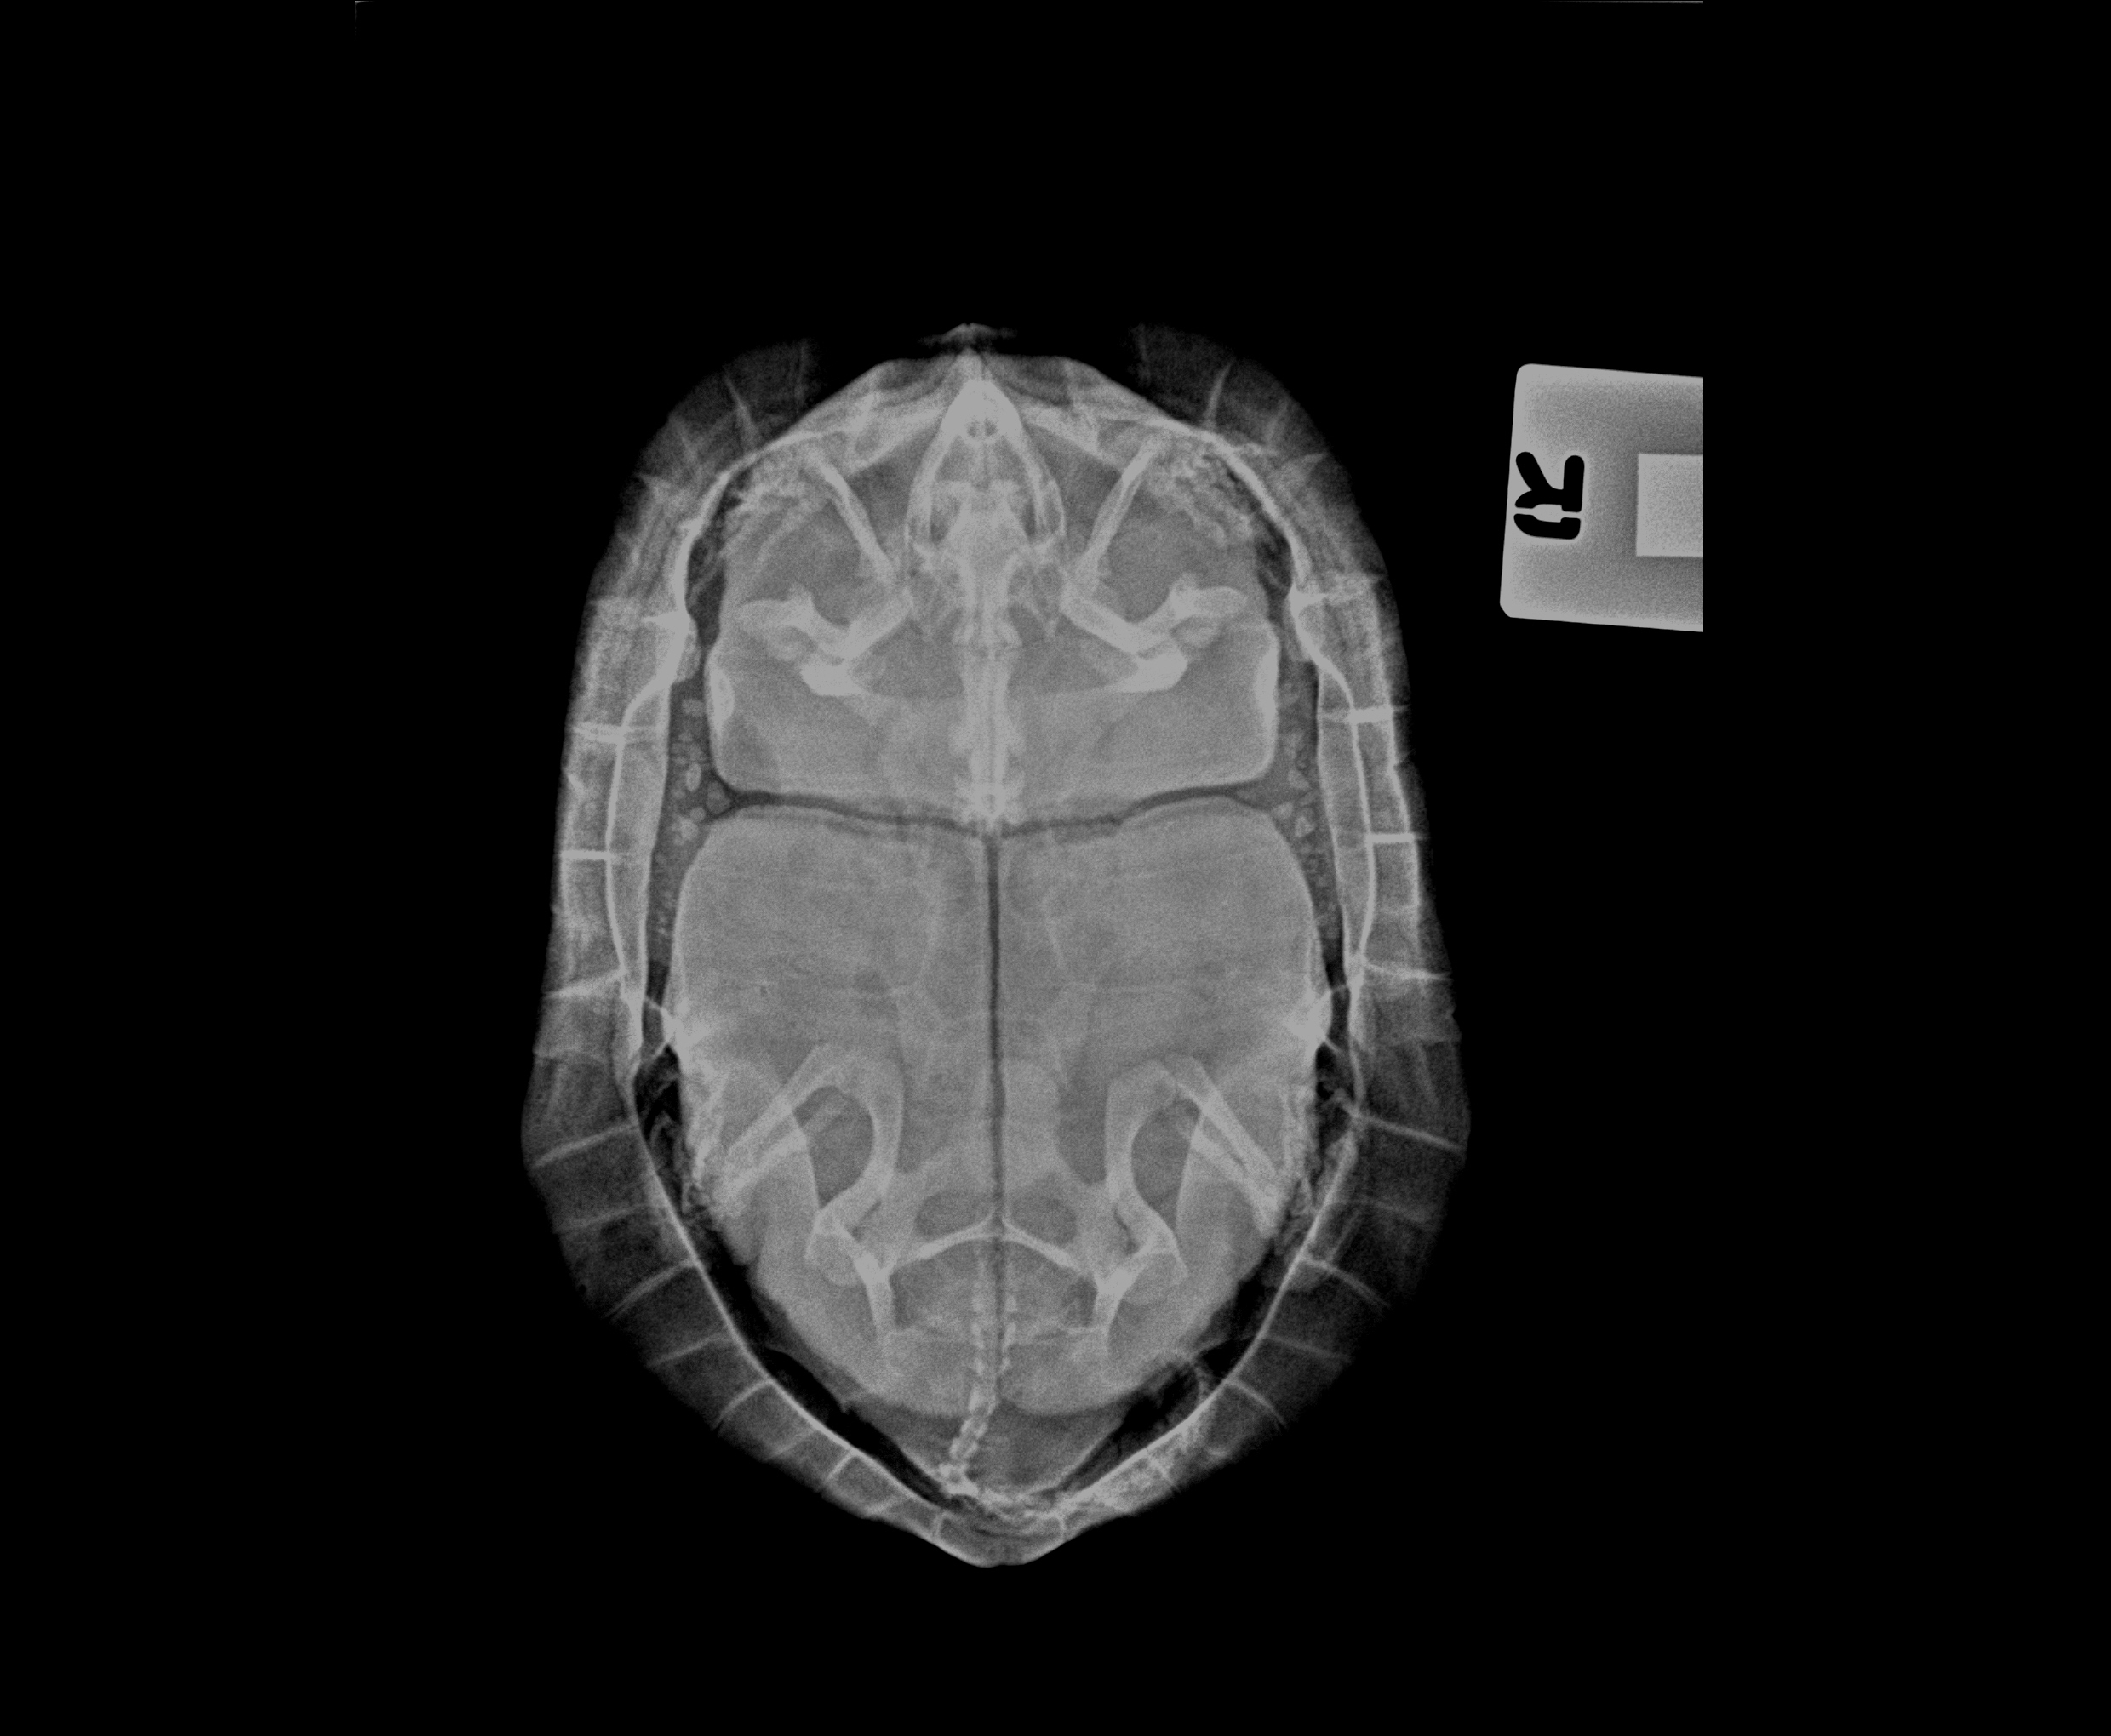

小寶是一隻年過三十的金錢龜(三線閉殼龜)。牠從小與婆婆一起居住。兩個月前,婆婆發現小寶食慾開始不振,慢慢變得完全不進食,活動也減少。她帶小寶到Jack's Vet時,我們發現牠嚴重脫水及十分虛弱。

經檢查後, 我們醫生發現小寶體內有一粒高密度的圓形物體,可能塞在腸、膀胱或是生殖管道,導致食慾不振及虛弱。

若果藥物治療未能解決問題,小寶可能需要動手術以取出該物體。

幸好,經過一個月的療程後,小寶順利排出那粒鈣化的膀胱石。排出阻礙物後,小寶恢復食慾,慢慢變得活躍。第二次療程完成後,小寶已經龍精虎猛了。恭喜小寶和牠的主人。